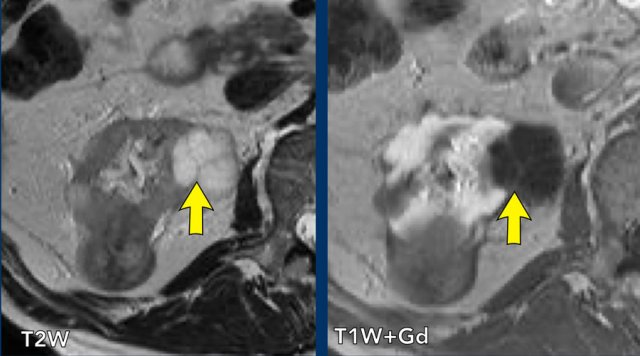

case 2

The images show a cystic mass with a thick walled (< 4mm) cyst with a few irregular thickened septa.

On the post contrast images there is no enhancement of the septa or wall but an enhancing mural nodule can clearly be identified (arrow).

This therefore represents a Bosniak IV lesion. The lesion was excised and proved to be a clear-cell carcinoma.